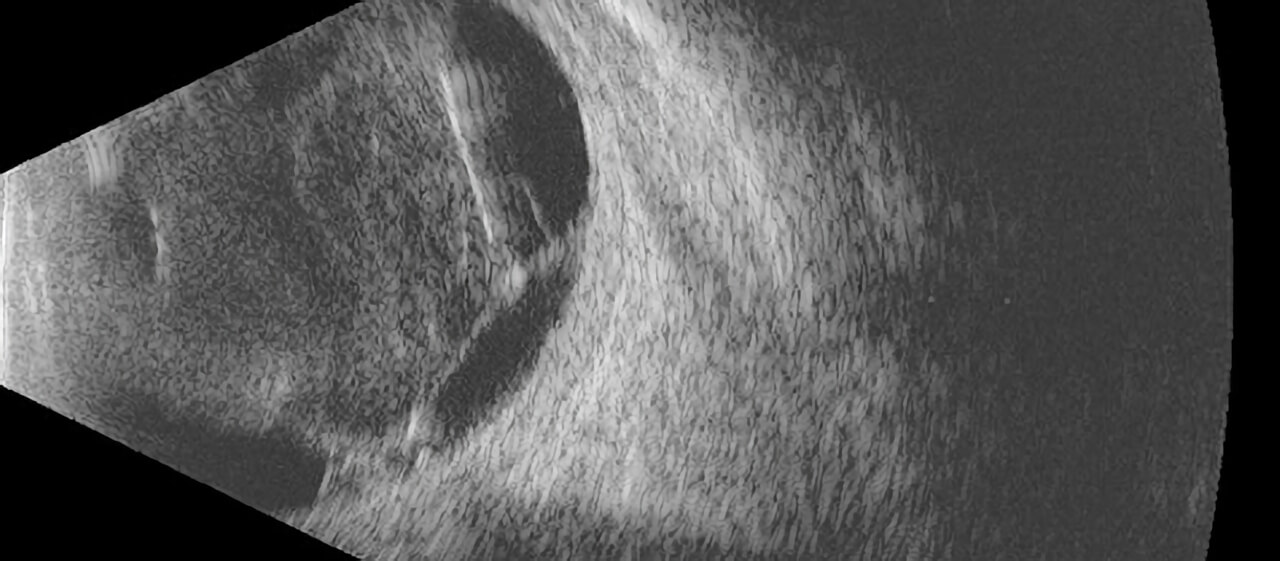

An ultrasound examination uses sound waves sent from a probe placed on the eye or eyelids to provide “sonar” images of the inside of the eye. The technology is very similar to the kind of ultrasound used to visualize other parts of the body, such as the liver or uterus. The sound waves are painless and harmless to the eye. The images can be printed or stored digitally so that they can be used for comparison on future examinations.

There are various ultrasound probes used for different purposes. These probes are designed to image and measure different parts of the eye. The most commonly used probe is the B-scan probe, which allows the doctor to view the internal structure of the eye through a dense cataract or hemorrhage inside the eye. We also have less commonly used probes, such as the diagnostic A-scan probe and anterior segment high frequency B-scan (also called ultrasound biomicroscopy). These probes are used in our practice primarily for the diagnosis and measurement of tumors inside the eye.